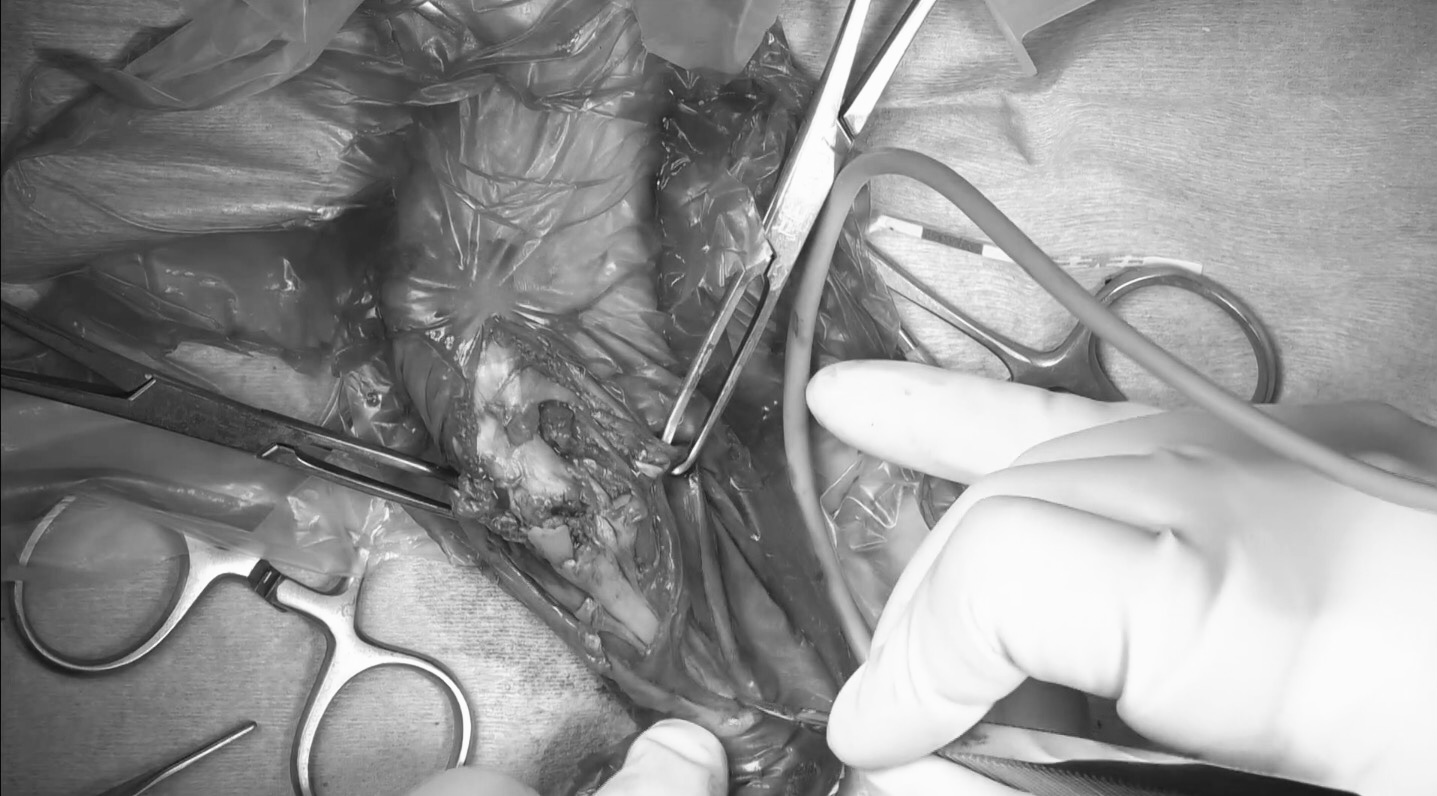

術中所見 術前のX線よりも骨折が複雑で骨片が多い印象を受けました